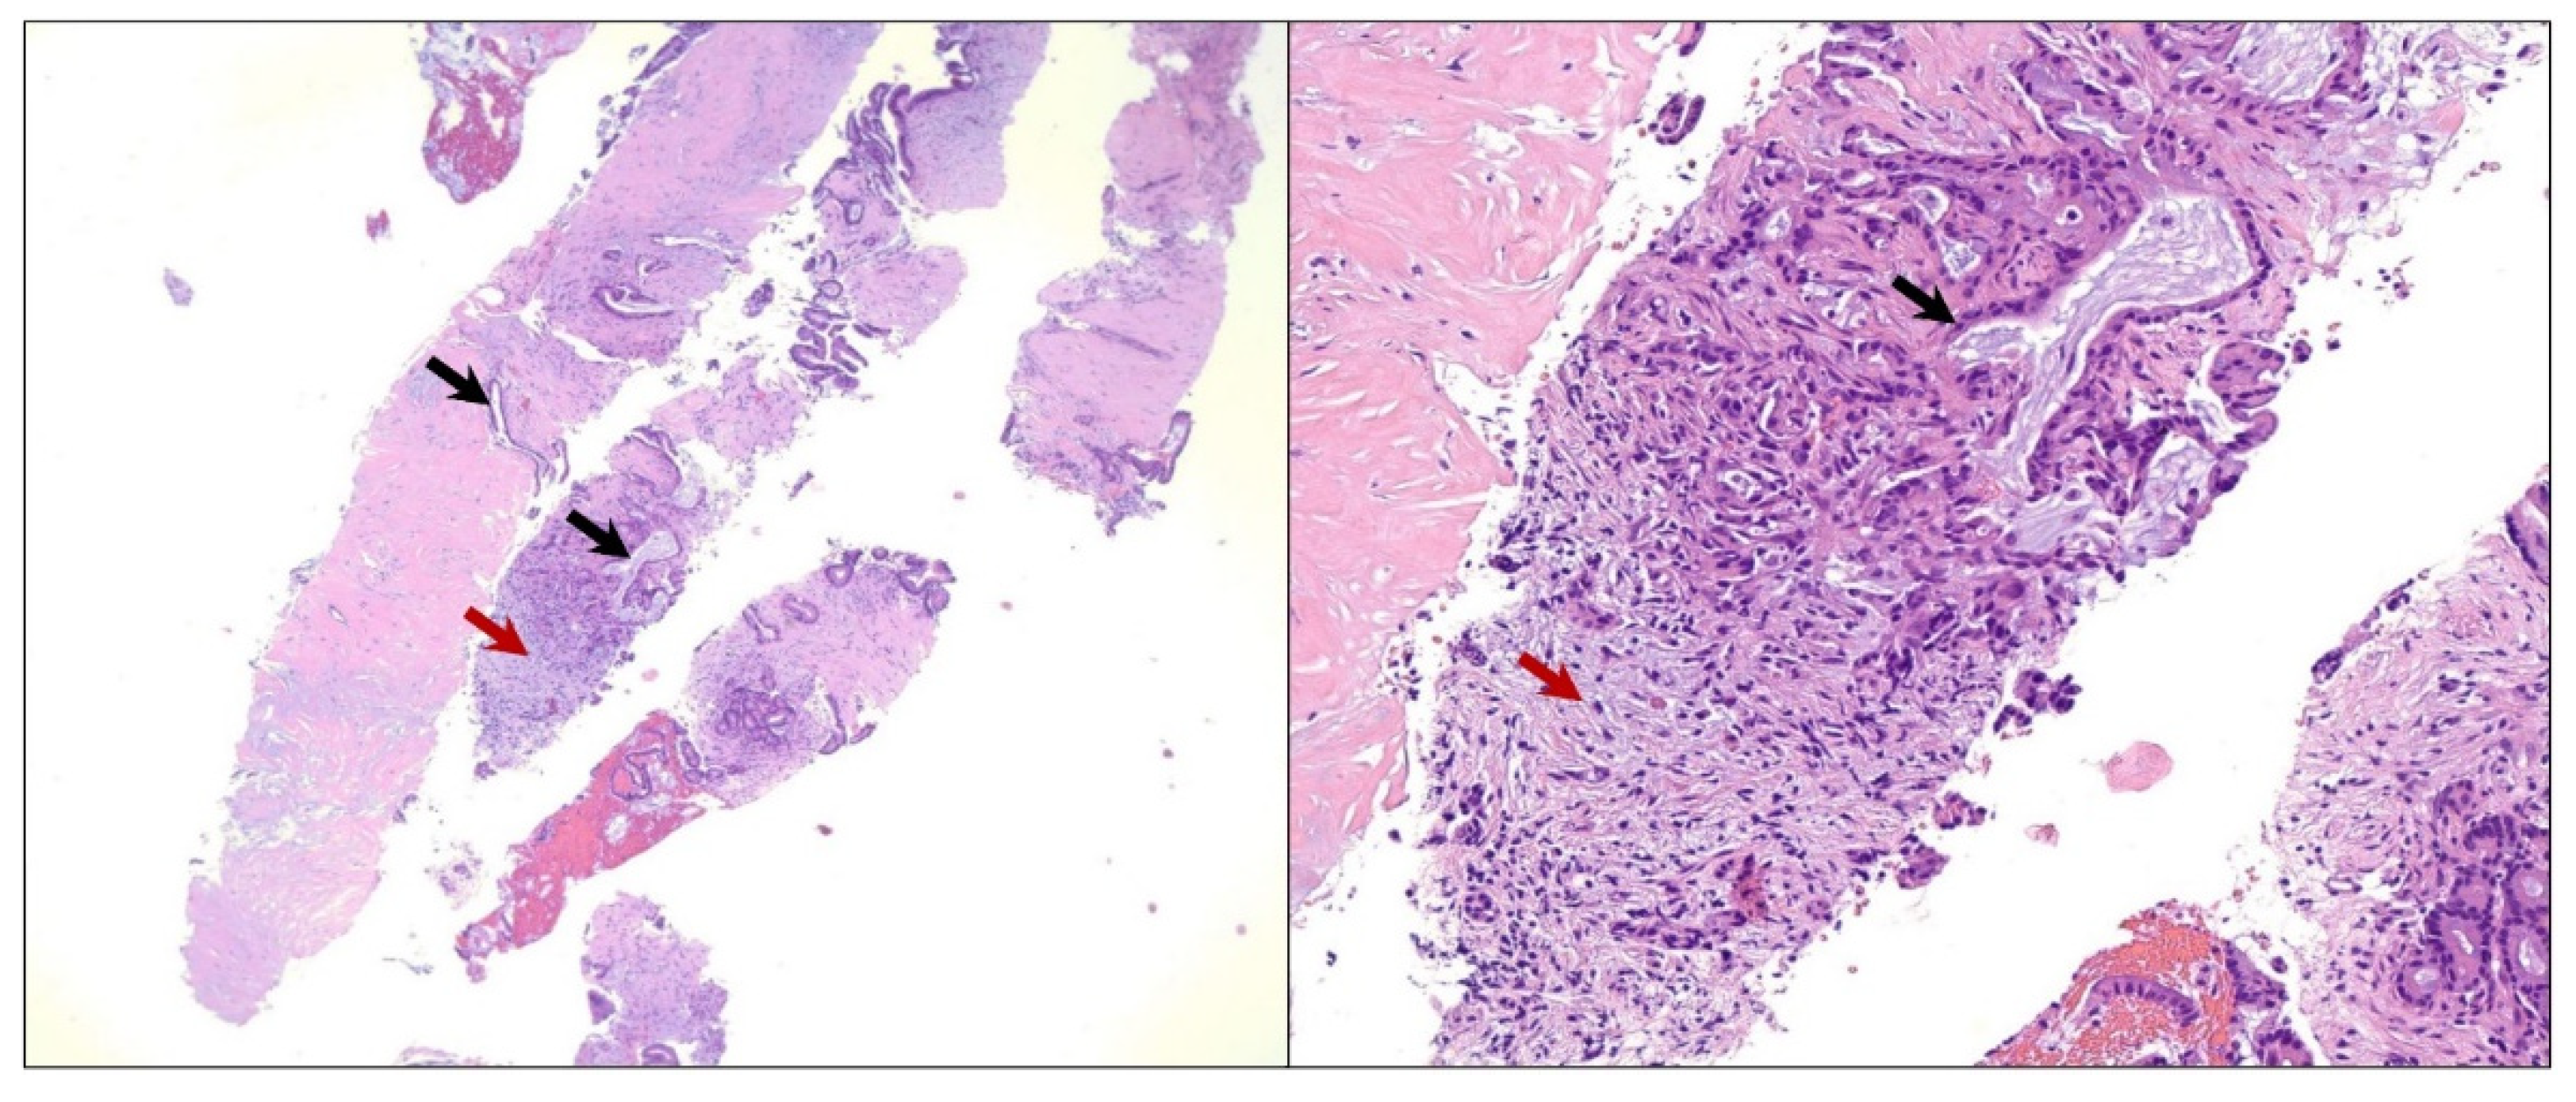

The patient underwent an upper gastroesophageal endoscopy (EGD) with endoscopic ultrasound (EUS), showing an approximately 3 cm hypoechoic mass extending from the neck to the body of the pancreas. An EUS-guided fine needle aspiration (FNA) was performed at an outside institution, and histopathologic examination revealed neoplastic epithelial cells forming glands that were infiltrating the pancreatic stroma (Figure 2). The neoplastic cells showed marked cytologic atypia, a high nuclear-cytoplasmic ratio, and nuclear pleomorphism. A diagnosis of primary moderately differentiated adenocarcinoma in the head of the pancreas was made.

Figure 2.

Microscopic image of the pancreatic fine needle aspiration specimen. Hematoxylin and eosin (H&E) staining showing neoplastic epithelial cells forming glands that are infiltrating the pancreatic stroma (black arrows). Also, a desmoplastic stromal reaction is seen (red arrows). The neoplastic cells show marked cytologic atypia, a high nuclear-cytoplasmic ratio, and nuclear pleomorphism, yielding a diagnosis of moderately differentiated adenocarcinoma in the head of the pancreas. Low-power magnification (40× objective) is shown in the panel to the left and high-power magnification (200× objective) is shown in the panel to the right.